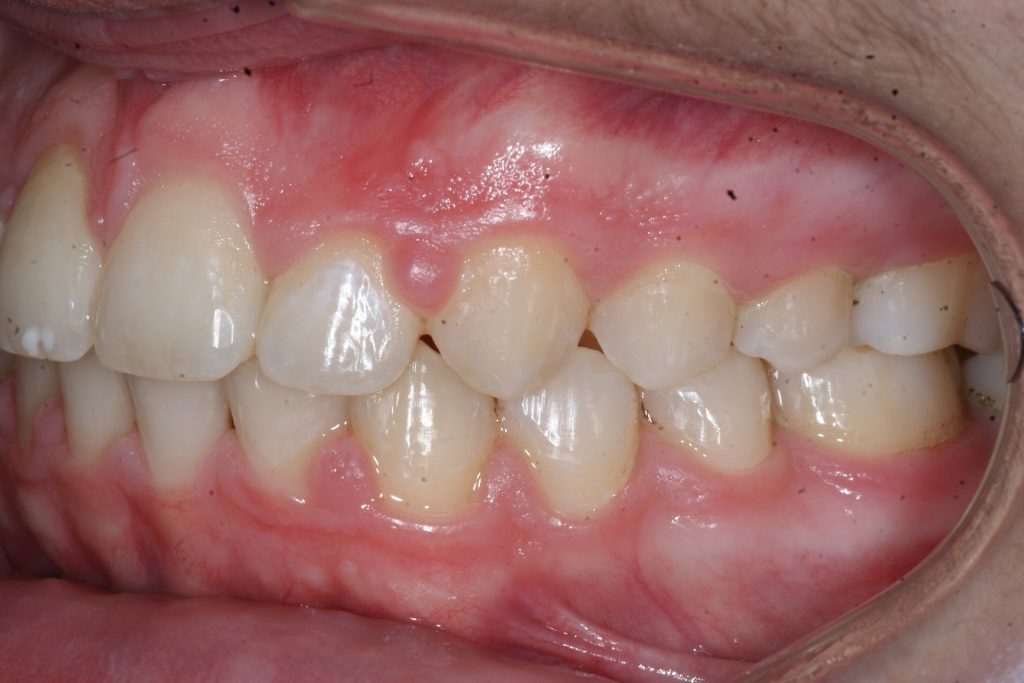

Correction d’une malocclusion de type Classe II.  Des appareils fixes (boîtiers) et une expansion palatine furent nécessaires pour améliorer ce sourire.  Traitement chez un adolescent, réalisé en 21 mois.